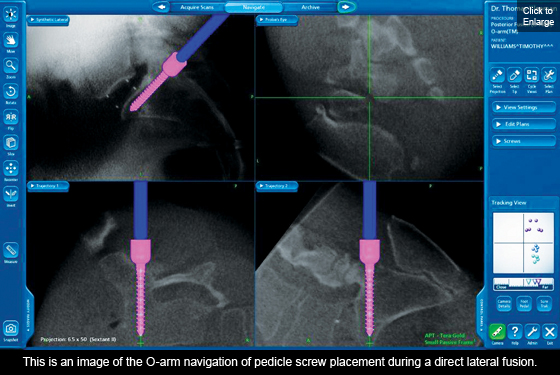

One of the most exciting new MIS techniques is the DLIF or "Direct Lateral Interbody Fusion". This technique requires a small 1" incision along the side of the abdomen allowing a bloodless approach to all levels of the lumbar spine except the lowest level L5-S1. Through this single incision it is often possible to correct complex multilevel deformity such as scoliosis.

L5-S1 is blocked from this direct lateral approach by the pelvis and since it is often involved in the pathology requiring a spinal fusion, a small innovative group of surgeons from around the country (including Dr. Thomas J. Kleeman from the New Hampshire Neurospine Institute) have been working together to solve this dilemma to allow L5-S1 to be accessed in a manner similar to the DLIF. This novel technique has been called the OLIF or "oblique lumbar interbody fusion". The OLIF is done "obliquely" (in front of the iliac crest) which gives direct access to L5-S1 while avoiding the back muscles (posterior fusion) and abdominal structures (anterior fusion). This approach allows us to use a single larger implant providing a larger fusion area and greater stability. Thus far, most of the patients were allowed to leave the hospital within 24 hours of their surgery. As with all procedures performed at NHNSI, we continually review the benefits and indications of this approach. We strive to provide the most effective and least invasive approaches to spine surgery. Our varied specialists provide us with a vast knowledge of techniques so we can bring you, the patient, the best solutions for your condition.